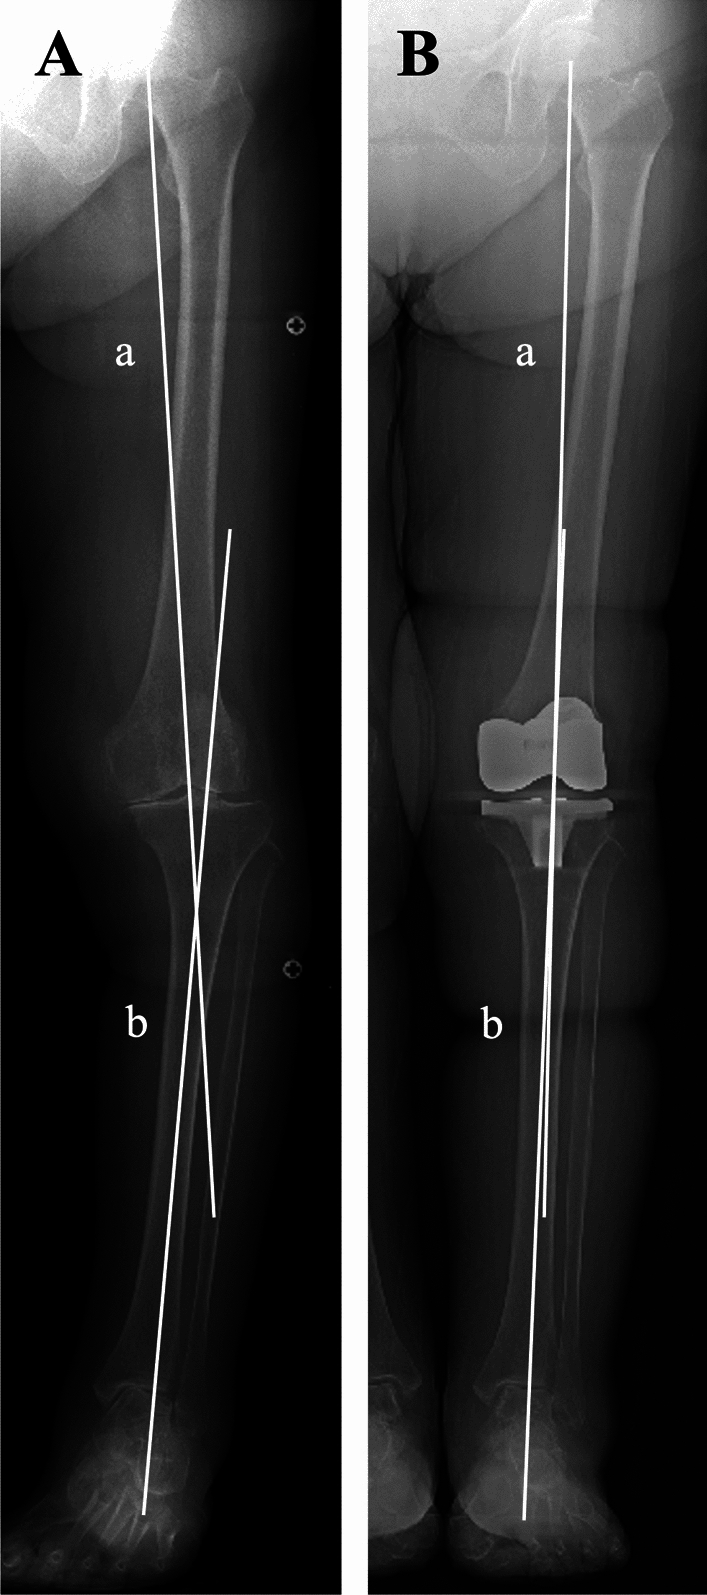

Methods: We retrospectively analyzed 331 patients who underwent unilateral mechanical alignment (MA) TKA for knee osteoarthritis. A control group of 40 healthy subjects was used to define normal alignment ranges. Whole-leg anteroposterior weight-bearing radiographs were obtained preoperatively and 2 months postoperatively. Alignment parameters included the hip-knee-ankle angle (HKA), tibiotalar tilt angle (TTA), tibial plafond inclination angle (TPIA), talar inclination angle (TIA), and hindfoot alignment angle (HAA). Pre- and postoperative values were compared using the Wilcoxon signed-rank test, and changes in the proportion of patients within the normal range were determined. Wilcoxon rank-sum tests and chi-squared tests were used for group comparisons, and multivariate logistic regression identified independent predictors of persistent malalignment.

Results: HKA improved after TKA (-12° to -2.0°), with corresponding improvements in TPIA (99° to 94°) and TIA (99° to 95°) (all p < 0.001), indicating a significant correction toward neutral alignment. The proportion of patients within normal range increased postoperatively from 16% to 85% for HKA, 26% to 67% for TPIA, 24% to 64% for TIA, and 65% to 73% for HAA. Multivariate analysis identified ankle OA (odds ratio [OR] = 6.62 for TTA), female sex (OR = 2.32 for TPIA; OR = 3.19 for TIA), and varus knee alignment (OR = 2.81 for TIA) as independent predictors of persistent malalignment.